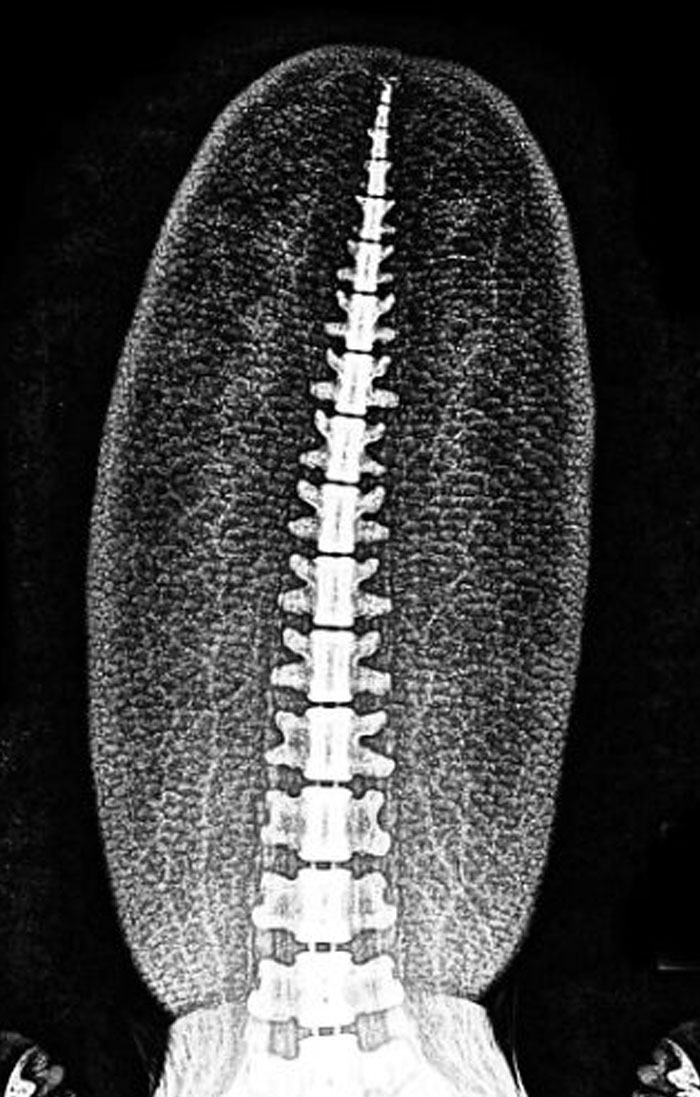

Here’s An X-Ray Of A Beaver’s Tail, And It’s Way Cooler Than You Thought

This x-ray reveals that if we only knew about beavers through fossils, we’d probably draw them all wrong (and that’s a big deal for how we imagine dinosaurs too). Animal artist C. M. Kosemen shows how bones alone don’t tell the whole story - soft stuff like fat and muscles make creatures look way different than just skinny skeletons.